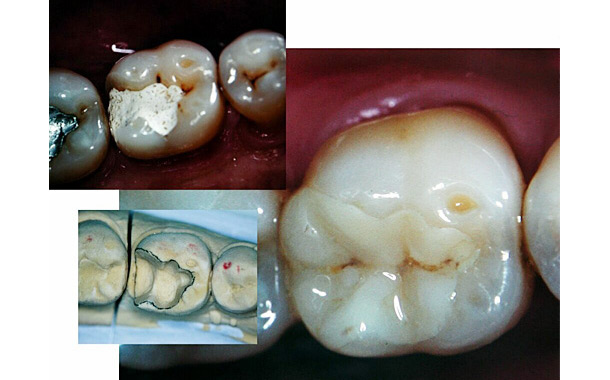

Avec les illustrations photographiques suivantes, vous pourrez voir comment cela se passe plus précisément: La dent initialement malade, puis la préparation de celle-ci, et enfin la mise en place de l’inlay esthétique venant combler le trou dans la dent.